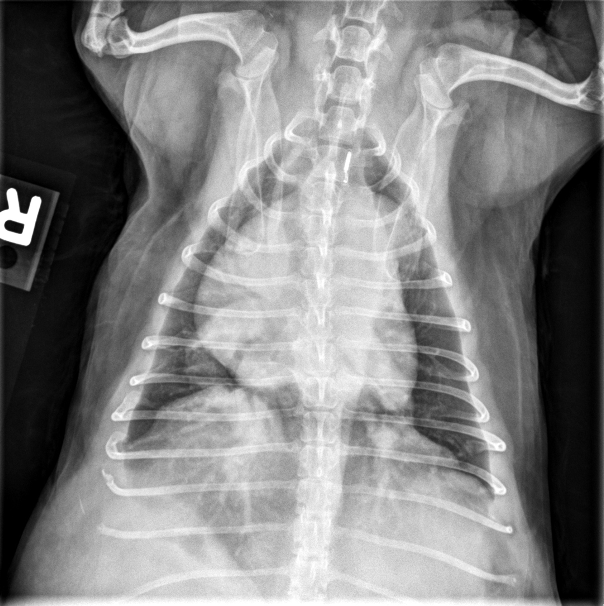

Dr. Anna Adrian, MS, DACVR, antwortet: Vielen Dank für die Zusendung dieses interessanten Falles. Es liegen eine links- und rechtslaterale sowie eine ventrodorsale Thoraxaufnahme vor. In allen drei Projektionen zeigt sich eine ausgeprägte rechtsseitige Kardiomegalie, die mit einer dorsalen Verlagerung der Trachea sowie einem vermehrten Kontakt des Herzens zum Sternum einhergeht (Bild 1, dunkelblaue Pfeilköpfe). In der ventrodorsalen Projektion imponiert die Rechtsherzvergrößerung als typische „reverse D-Form“ (Bild 2, dunkelblaue Pfeile). Zusätzlich fällt in dieser Ansicht auf Höhe der 2-Uhr-Position eine Vorwölbung auf, die einer Dilatation des Truncus pulmonalis entspricht (Bild 2, dunkelblauer Kreis).

Die kaudalen lobären Pulmonalarterien sind hochgradig erweitert, überschreiten deutlich die Breite der 9. Rippe und zeigen einen geschlängelten Verlauf (Bild 1 und 2, hellblaue Pfeile). Zur Erinnerung Venen liegen in der VD-Aufnahme zentral und in der lateralen Aufnahme ventral, wohingegen Arterien lateral und dorsal gelegen sind. Die Vena cava caudalis erscheint geringgradig dilatiert. Das Lungenparenchym weist insgesamt ein leicht- bis mittelgradig ausgeprägtes bronchointerstitielles Muster auf. Im kranialen Abdomen ist eine kraniale abdominale Organomegalie erkennbar, sowie geringgradige Heterogenität des abdominalen Fettgewebes (Bild 1, hellblau gestricheltes Rechteck). Dieser Befund ist vereinbar mit einer Splenomegalie +/- Hepatomegalie und geringgradiger Aszites. Die übrigen abdominalen Strukturen erscheinen unauffällig.